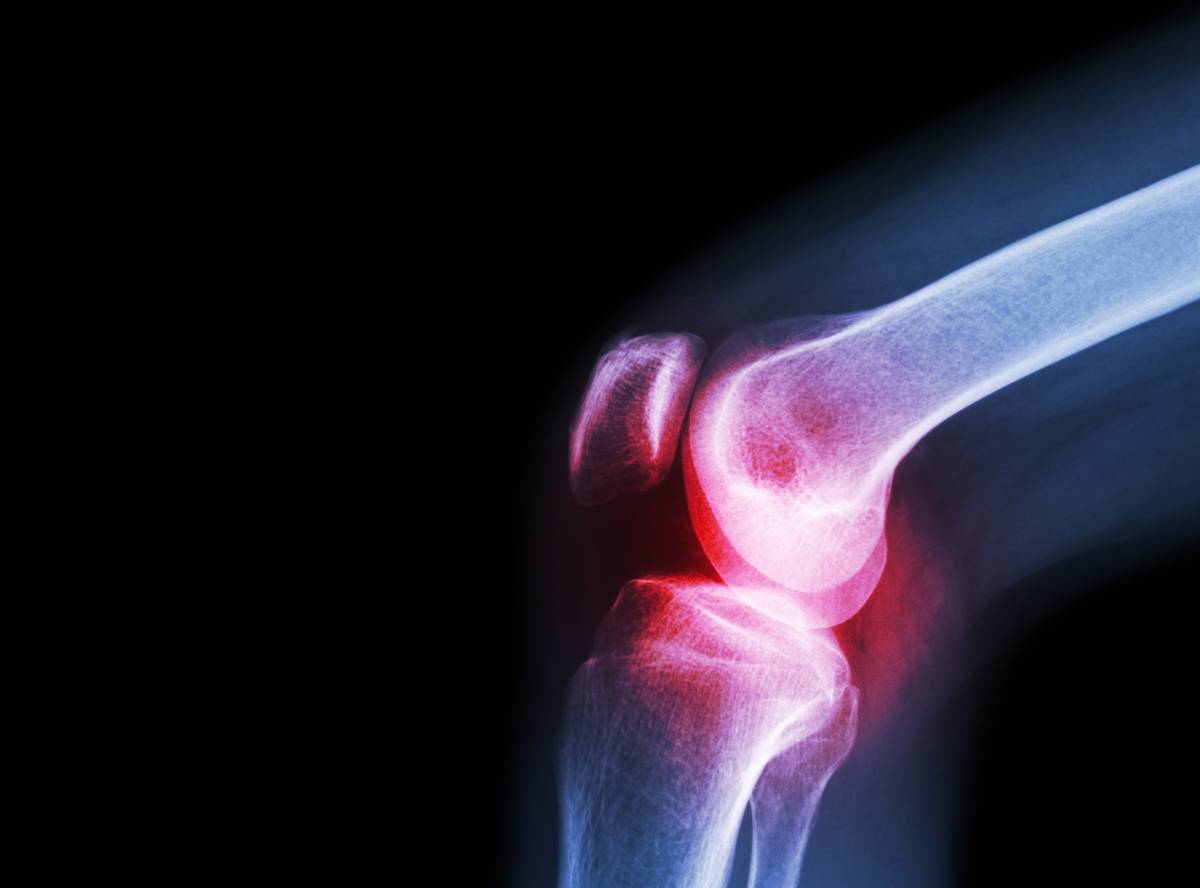

2021-10-13 12:24:00关节炎泛指发生在人体关节及其周围组织的炎性疾病,包括骨关节炎、类风湿关节炎、感染性关节炎、代谢性关节炎(如痛风)等。我国的关节炎患者有1亿以上,且人数还在不断增加。对于关节炎患者而言,除了遵医嘱治疗,更重要的是要做好日常护理。

其次,在关节炎发作期间,针对不同症状,采取对症治疗,能帮助减缓关节炎症状。包括用止痛药(如对乙酰氨基酚)减轻疼痛,非甾体抗炎药(如萘普生)减轻疼痛和炎症。还可将皮质类固醇药物(如强的松)直接注射到关节腔,减轻炎症和抑制免疫系统。物理疗法包括热疗、经皮神经电刺激等,可改善局部的血液循环,改善肌张力,缓解关节炎引起的疼痛。在慢性期进行物理疗法还可预防复发。

当然,不同类型的关节炎在治疗上还是会有些差异。如感染性关节炎,可能需要结合药敏试验选用抗生素;骨关节炎的治疗目的主要是缓解疼痛,延缓疾病进展,到了后期可能需要关节重建手术治疗。